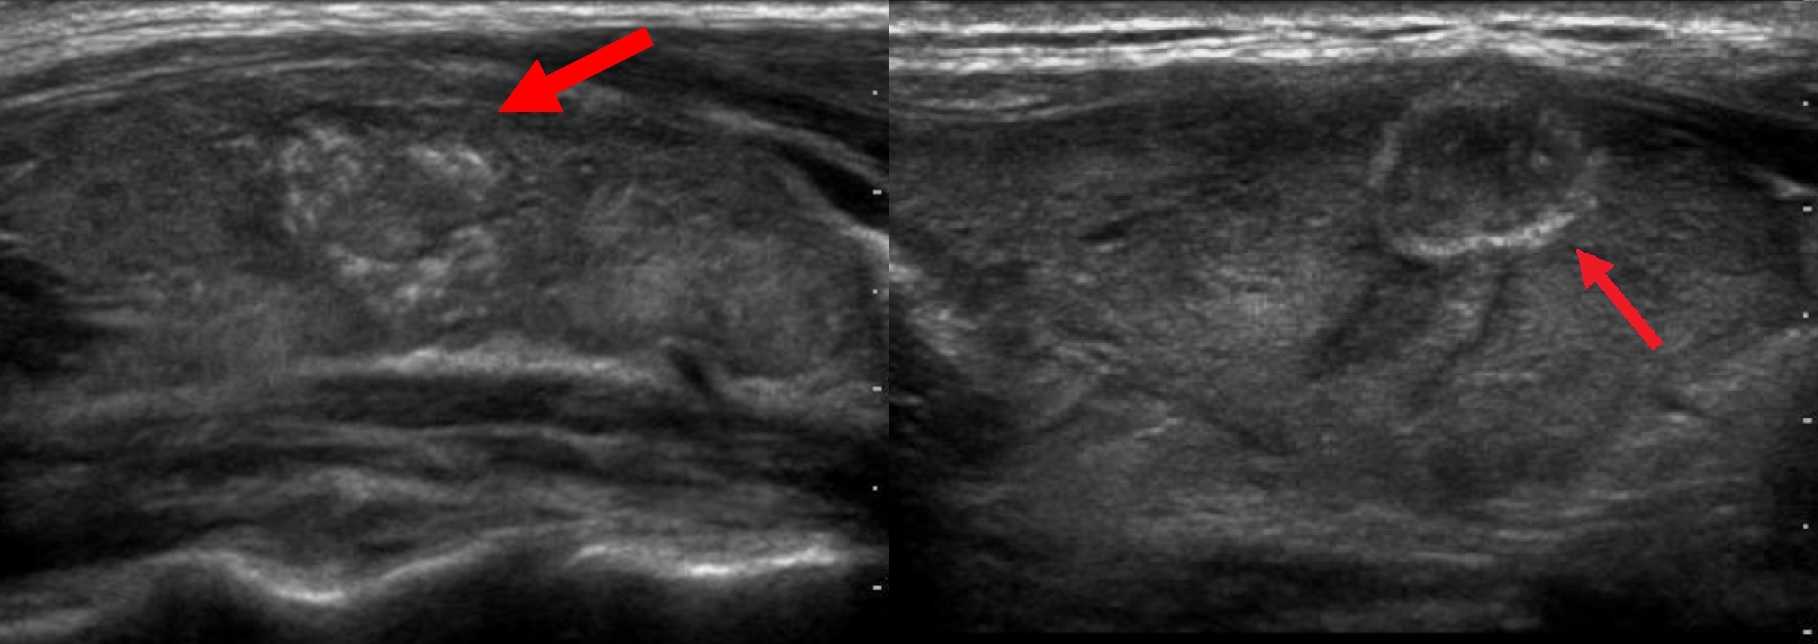

Рисунок. У пациентов с тиреотоксикозом на УЗИ щитовидная железа диффузно увеличена, гипоэхогенная, неоднородная; в правой доле определяется гипоэхогенный очаг (более 10 мм) с гиперэхогенной неравномерной капсулой, интранодулярные точечные гиперэхогенные включения (псаммомные тельца). Заключение по результатам биопсии: Папиллярная карцинома на фоне ДТЗ.